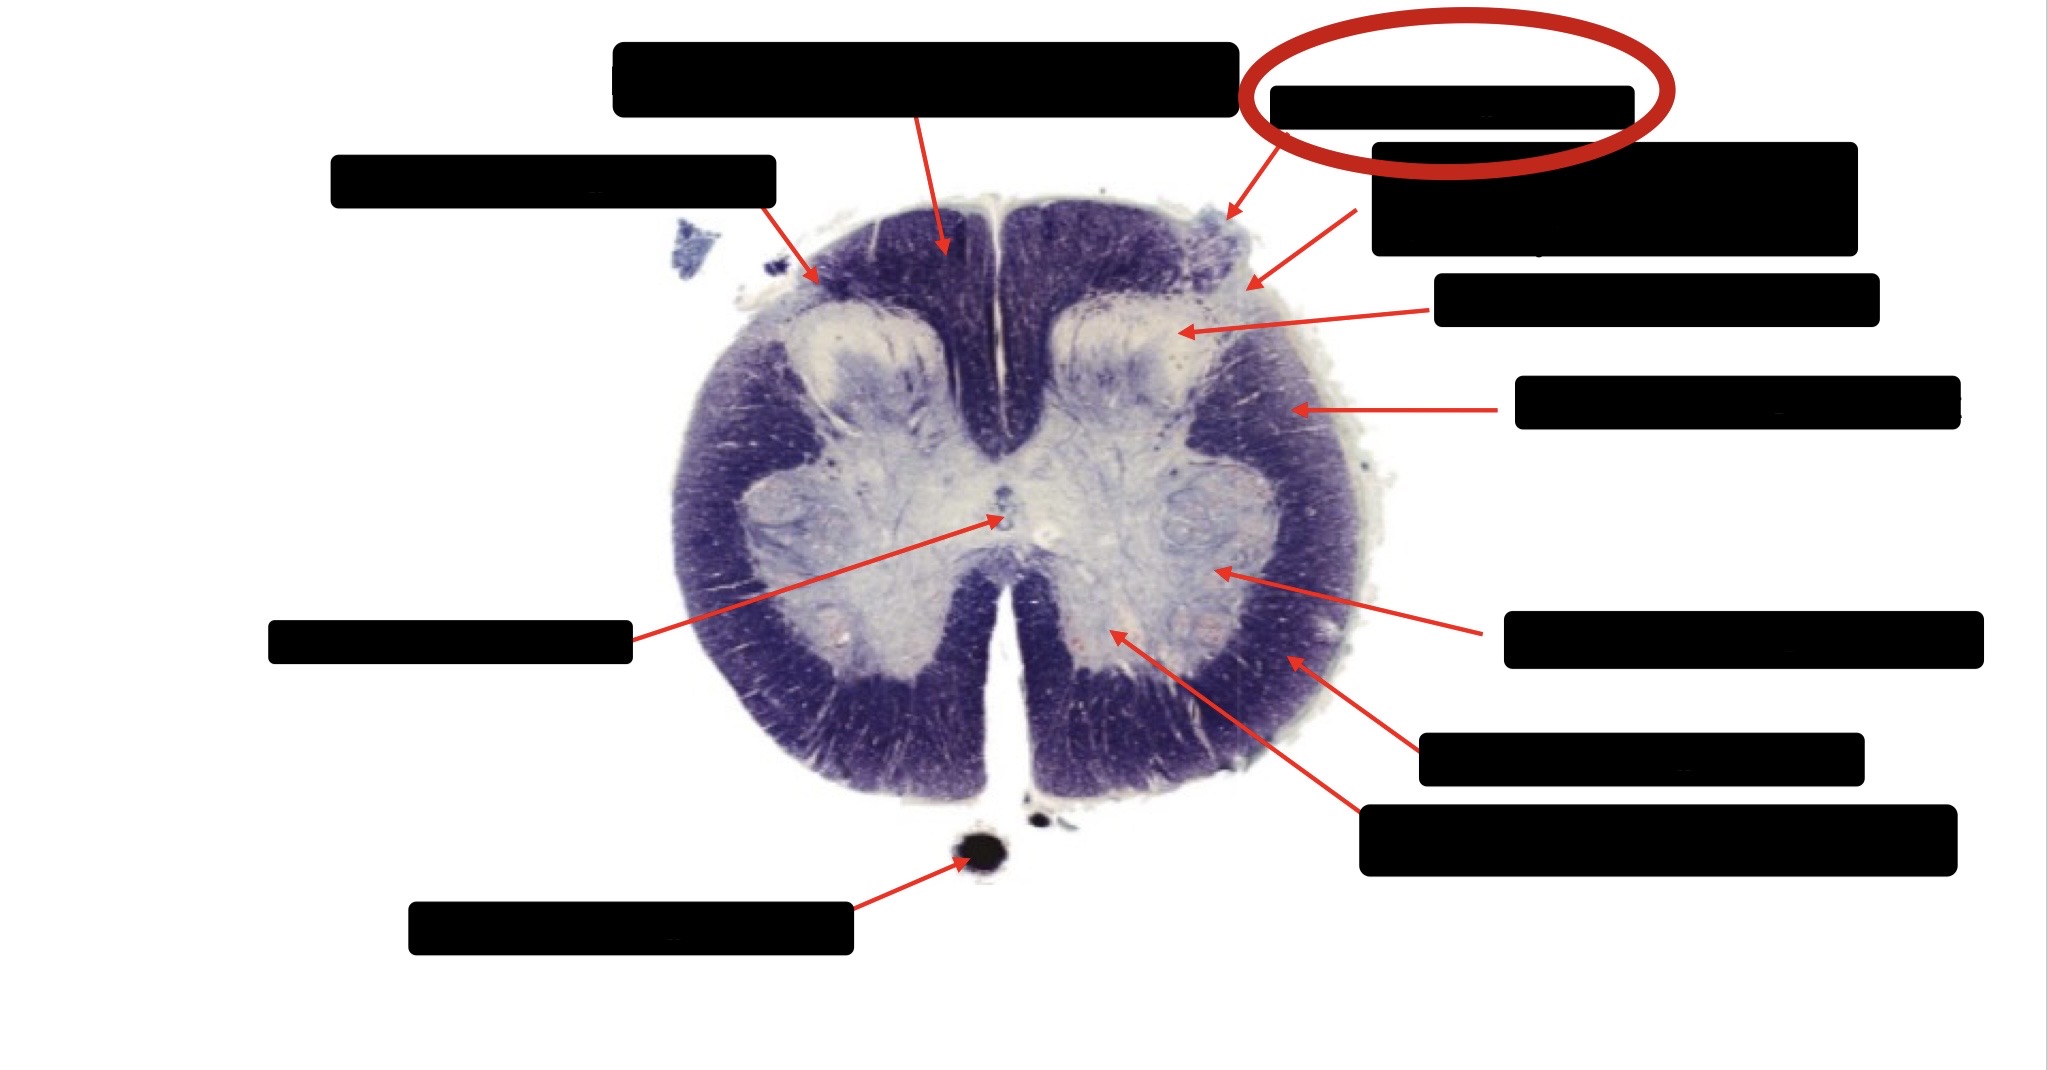

Anterior Spinal Artery

Denticulate Ligament

Ventral Root

Dorsal Root

Posterior Column Fasciculus Gracilis

Large Fiber Entry Zone

Central Canal

Dorsal Rootlet

Lissaeur’s Tract & Small Fiber Entry Zone

Substantia Gelatinosa

Lateral Corticospinal Tract

Anterior Horn Motor Neuron

Spinothalmic Tract